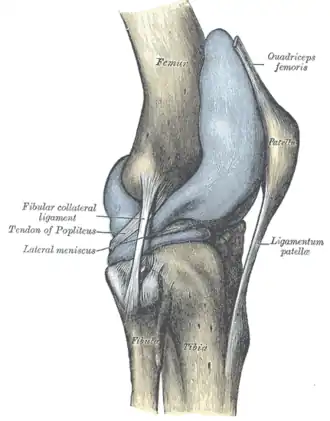

Lateral aspect of right knee -

Ligaments

The ligaments surrounding the knee joint offer stability by limiting movements and, together with the menisci and several bursae, protect the articular capsule.[19]

Intracapsular

The knee is stabilized by a pair of cruciate ligaments. These ligaments are both extrasynovial, intracapsular ligaments.[20] The anterior cruciate ligament (ACL) stretches from the lateral condyle of femur to the anterior intercondylar area.[13] The ACL prevents the tibia from being pushed too far anterior relative to the femur.[13] It is often torn during twisting or bending of the knee.[21] The posterior cruciate ligament (PCL) stretches from medial condyle of femur to the posterior intercondylar area. This ligament prevents posterior displacement of the tibia relative to the femur.[13] Injury to this ligament is uncommon but can occur as a direct result of forced trauma to the ligament.

The transverse ligament stretches from the lateral meniscus to the medial meniscus. It passes in front of the menisci. It is divided into several strips in 10% of cases.[10]: 208 The two menisci are attached to each other anteriorly by the ligament.[22] The posterior (of Wrisberg) and anterior meniscofemoral ligaments (of Humphrey) stretch from the posterior horn of the lateral meniscus to the medial femoral condyle. They pass anterior and posterior to the posterior cruciate ligament respectively.[13][10]: 208 The meniscotibial ligaments (or "coronary") stretches from inferior edges of the menisci to the periphery of the tibial plateaus.

Extracapsular

The patellar ligament connects the patella to the tuberosity of the tibia. It is also occasionally called the patellar tendon because there is no definite separation between the quadriceps tendon (which surrounds the patella) and the area connecting the patella to the tibia.[23] This very strong ligament helps give the patella its mechanical leverage[24] and also functions as a cap for the condyles of the femur. Laterally and medially to the patellar ligament, the lateral and medial retinacula connect fibers from the vasti lateralis and medialis muscles to the tibia. Some fibers from the iliotibial tract radiate into the lateral retinaculum and the medial retinaculum receives some transverse fibers arising on the medial femoral epicondyle.[10]: 206

The medial collateral ligament (MCL a.k.a. "tibial") stretches from the medial epicondyle of the femur to the medial tibial condyle. It is composed of three groups of fibers, one stretching between the two bones, and two fused with the medial meniscus. The MCL is partly covered by the pes anserinus and the tendon of the semimembranosus passes under it.[10]: 206 It protects the medial side of the knee from being bent open by a stress applied to the lateral side of the knee (a valgus force).[10]: 206

The lateral collateral ligament (LCL a.k.a. "fibular") stretches from the lateral epicondyle of the femur to the head of fibula. It is separate from both the joint capsule and the lateral meniscus.[10]: 206 It protects the lateral side from an inside bending force (a varus force). The anterolateral ligament (ALL) is situated in front of the LCL.

Lastly, there are two ligaments on the dorsal side of the knee. The oblique popliteal ligament is a radiation of the tendon of the semimembranosus on the medial side, from where it is direct laterally and proximally. The arcuate popliteal ligament originates on the apex of the head of the fibula to stretch proximally, crosses the tendon of the popliteus muscle, and passes into the capsule.[10]: 206